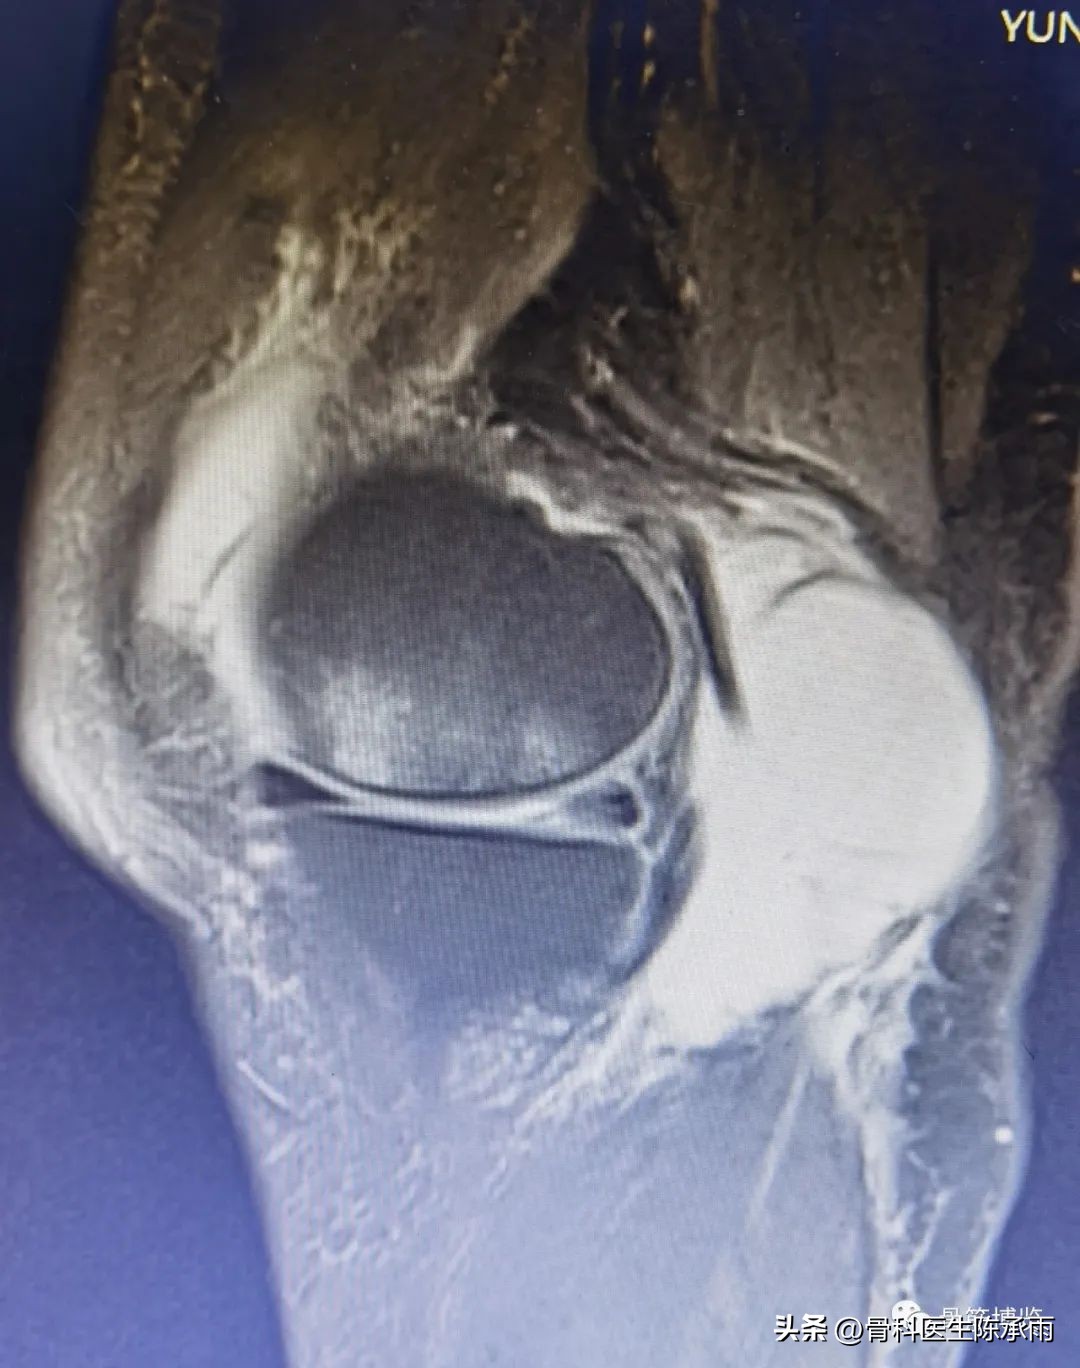

术前影像

腘窝囊肿又被称为 Baker囊肿,是一种囊性肿块,常由腘窝处肌腱滑囊囊壁扩张引起,最常见的是腓肠肌半膜肌滑囊。通过股骨髁内侧后方关节囊开口,腘窝囊肿与膝关节相通。多种理论认为,此开口在出现关节积液时会产生阀门机制,进而发展成腘窝囊肿,这种交通性囊肿常含有滑液。成人腘窝囊肿通常继发于退行性或炎性关节病或关节损伤,如骨关节炎、半月板撕裂、类风湿关节炎等。儿童腘窝囊肿通常是直接起源于腓肠肌-半膜肌滑囊的原发性疾病,不与关节间隙相通。腘窝囊肿的表现既可以是长期慢性、反复发作,也可表现为急性发作。而囊肿破裂会出现假性血栓性静脉炎。超声和MRI可精确诊断腘窝囊肿。

镜下囊肿切除∶镜头进入后间室,膝关节放置"4"字位,探针探查腘窝囊肿与关节腔的交通口,通常位于腘窝囊肿前方后内侧关节囊皱襞上。通过后内侧入路用刨削器将后内侧关节囊皱襞清除,充分地扩大腓肠肌内侧头与半膜肌之间的交通口,并清理增生的束带组织,使得腘窝囊肿和关节腔之间的滑囊液可以双向流动。充分显露腓肠肌内侧头,可于腓肠肌内侧头与半膜肌之间暴露出腘窝囊肿,通过关节镜对腘窝囊肿进行关节腔内引流。将刨削器和关节镜伸入囊肿内部清理囊腔,屈曲膝关节至"4"字位,从外侧挤压囊肿位置,从而使囊壁更易切除。也可以在手术前向腘窝囊肿内注射亚甲蓝 2ml,可在镜下更好显示囊肿,完全切除亚甲蓝染色的囊壁、囊内分割部分和可能的多发性囊肿的囊壁。